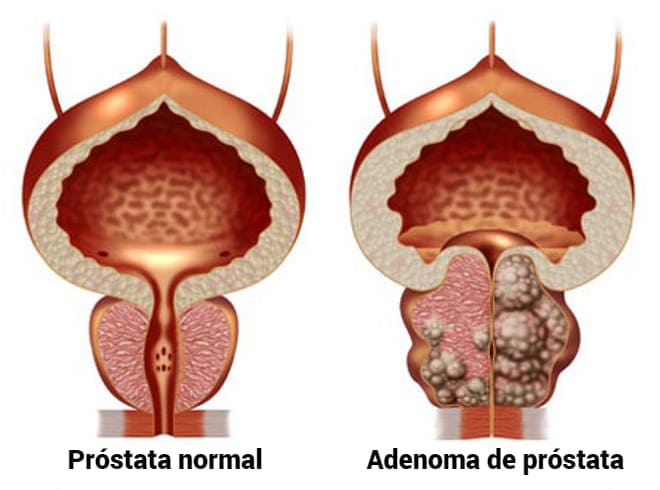

En los últimos años, las estadísticas de enfermedades urológicas han superado el número de enfermedades de los órganos circulatorios. Después de 50 años de adenoma (tumor benigno) de la próstata se encuentra en 20-25%, y a los 60 años, el 50% de los hombres. La incidencia de cáncer de próstata recientemente ha alcanzado el primer lugar entre los cánceres masculinos. Todas estas consecuencias de la disfunción eréctil progresa debido a la desnutrición. Los alimentos grasos pesados, los alimentos modificados genéticamente y el tabaco y el alcohol de baja calidad causan daños irreparables a la salud de los hombres.

- Por desgracia, sí. Muchas enfermedades masculinas, como el adenoma y el cáncer de próstata, se "vuelven más jóvenes"dramáticamente. Si antes era un problema de pacientes de edad, ahora cada vez más diagnosticamos estas enfermedades en pacientes a partir de los 40 años. Además, en los últimos 30 años, la infertilidad masculina ha aumentado muy dramáticamente. Según las estadísticas mundiales, una de cada diez parejas casadas resulta estéril, es decir, incapaz de concebir un hijo sin la ayuda de la medicina. En el 45% de los casos, el hombre es "culpable". Todo esto se debe a la disfunción eréctil, es decir incapacidad para lograr la erección necesaria para tener relaciones sexuales. Si un hombre no siempre puede lograr una erección, esto indica el comienzo cambios difíciles reversibles en su sistema reproductivo y, como resultado, abre el camino para las enfermedades concomitantes más graves, tales como prostatitis y adenoma de próstata. En el 90% de los casos, el adenoma de próstata no se puede tratar y es fatal.

Siempre es el resultado de la falta de sexo, por lo que el adenoma es una enfermedad de los ancianos.